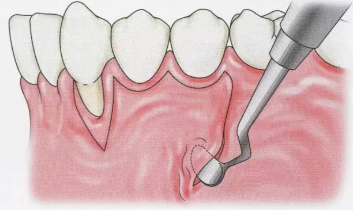

牙周手术的减张切开法

牙周手术的减张切开法!